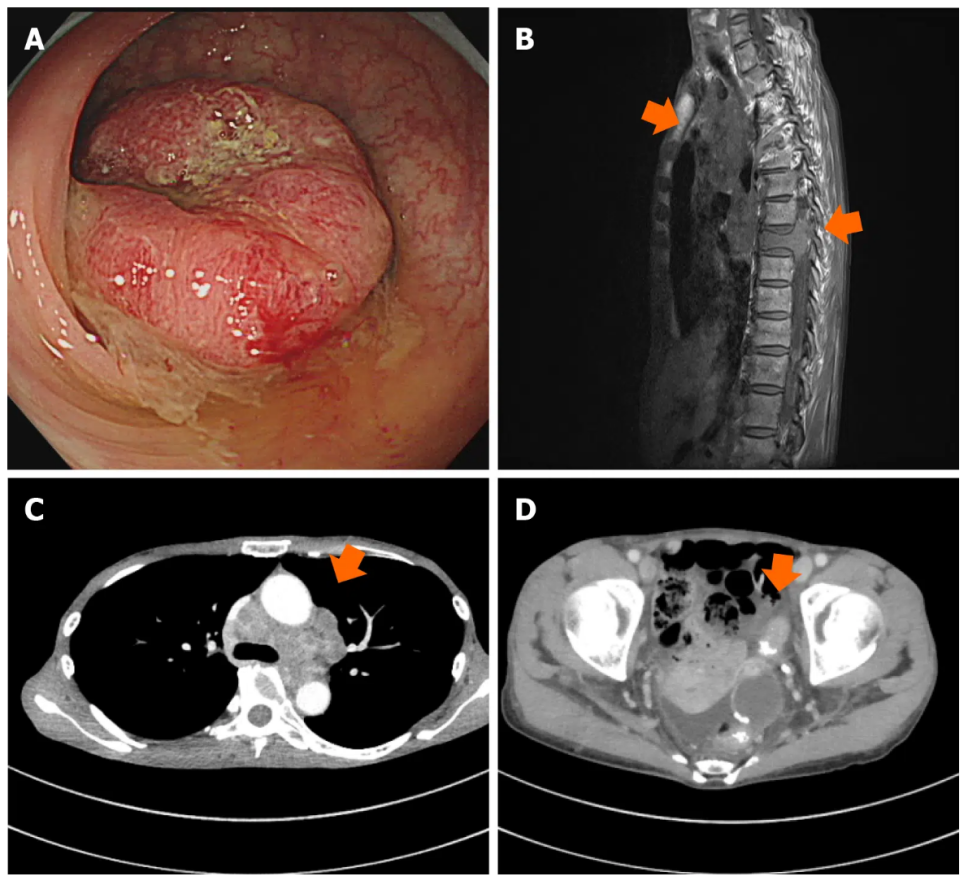

化疗前进行的结肠镜检查显示乙状结肠癌晚期,病理组织标本中检出分化型腺癌(图1)。肿瘤组织的伴随诊断结果显示为RAS/BRAF野生型,且不存在微卫星不稳定性。根据恶性肿瘤的TNM分期系统(第8版),患者的临床分期为cT3N3M1。

图1. 治疗前影像学检查结果。A:乙状结肠结肠镜图像;B:纵隔淋巴结和脊柱骨的磁共振图像;C和D:纵隔淋巴结和乙状结肠的计算机断层扫描图像